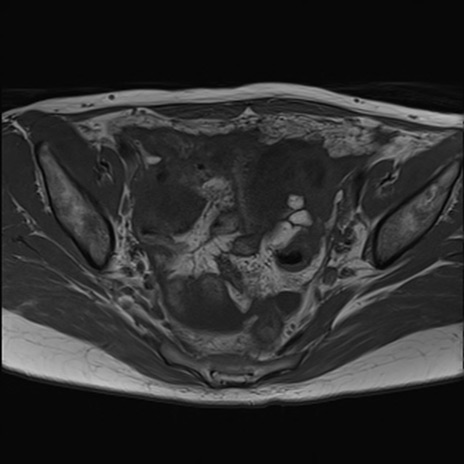

症例39 T1WI(横断像)

MRI(4日後)